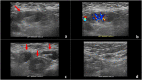

With the recent U.S. Food and Drug Administration (FDA)-approval and rollout of the Pfizer-BioNTech and Moderna COVID-19 vaccines, it is important for radiologists to consider recent COVID-19 vaccination history as a possible differential diagnosis for patients with unilateral axillary adenopathy. Hyperplastic axillary nodes can be seen on sonography after any vaccination but are more common after a vaccine that evokes a strong immune response, such as the COVID-19 vaccine. As the differential of unilateral axillary adenopathy includes breast malignancy, it is crucial to both thoroughly evaluate the breast for primary malignancy and to elicit history of recent vaccination. As COVID-19 vaccines will soon be available to a larger patient population, radiologists should be familiar with the imaging features of COVID-19 vaccine induced hyperplastic adenopathy and its inclusion in a differential for unilateral axillary adenopathy. Short-term follow-up for unilateral axillary adenopathy in the setting of recent COVID-19 vaccination is an appropriate recommendation, in lieu of immediately performing potentially unnecessary and costly axillary lymph node biopsies.